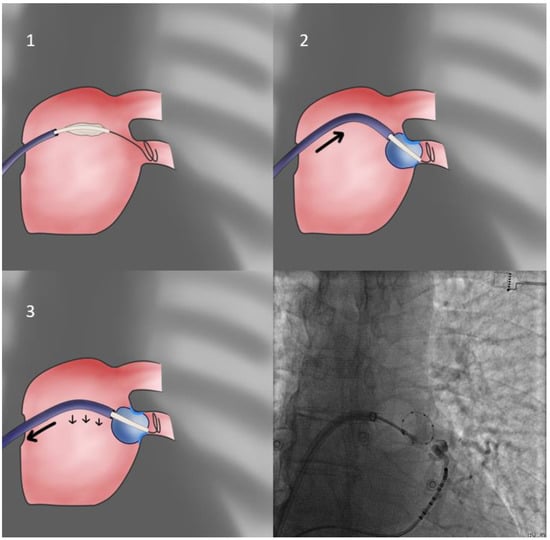

- When, despite all efforts and maneuvers already described, the operator cannot achieve proper alignment of the Achieve/CB/sheath system with the vein, a final solution entails allowing the PV itself to position the CB in its antrum. This is achieved by purposefully and warily inflating slightly inside the PV ostium (obviously the operator must be alert and retract the system if severe CB distortion is observed), whilst the sheath is placed in the approximately anticipated orientation, slightly flexed in order to be rigid. It is expected that the PV will eject the inflating balloon while imparting its orientation to it—thus, the operator must be vigilant and immediately use the prepped sheath to intercept the motion and achieve apposition of the CB to the antrum in the vein-determined orientation (trap-based approach—Figure 5). If more pressure is needed to achieve occlusion, it is more prudent to use the balloon catheter shaft since pushing the rigid sheath may undo the achieved proper orientation of the system.